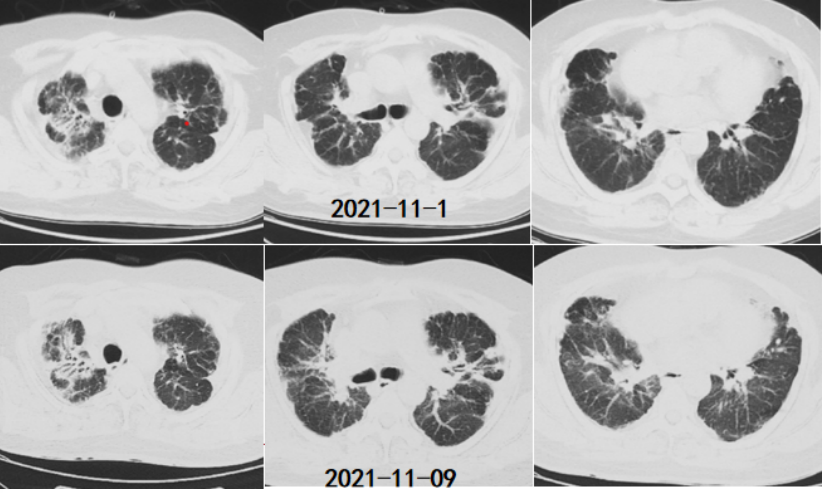

第3次住院(2020年12月7-13日):12月7日“受凉”后再次咳喘加重,于当地县医院住院。12月13日胸部CT:右肺上叶支气管束增厚,双肺胸膜下斑片影,双侧胸膜增厚,较前变化不明显(图5)。诊断为“肺炎,支气管扩张”。咳喘症状减轻,出院后继续口服醋酸泼尼松15 mg qd(图6),于2021年1月自行停药(约20 d),患者仍间断咳嗽,伴活动后气短,但可正常从事超市相关工作。

第4次住院(2021年10月24日-11月17日):2021年10月9日(停用激素后8个月)患者因“受凉”后咳喘加重,平地步行20 m即喘息明显,伴发热,体温最高38.5℃,痰中带血丝,约数口。当地诊所给予地塞米松(5 mg qd)治疗15 d,无明显改善,入当地县医院ICU住院,入院时测SpO2(未吸氧)60%。10月26日胸部CT:双肺弥漫磨玻璃影,散在斑片影,部分融合呈实变,双上肺胸膜增厚,较前明显加重(图7)。患者血气分析提示Ⅱ型呼吸衰竭,低氧血症明显,伴二氧化碳潴留,WBC和NEU升高,经治疗有所下降;生化指标可见LDH水平升高(表1~表3)。

诊断“间质性肺炎,慢阻肺急性加重期,支气管扩张,Ⅱ型呼吸衰竭”。抗感染20 d,激素治疗20 d(图9),鼻导管氧疗及NPPV。咳嗽、喘息明显减轻。胸部CT:对比10月26日,双肺斑片影、磨玻璃影明显吸收(图10)。11月17日评估病情好转出院,出院后继续口服甲泼尼龙12 mg qd(11月17-30日,13 d后自行停药)。